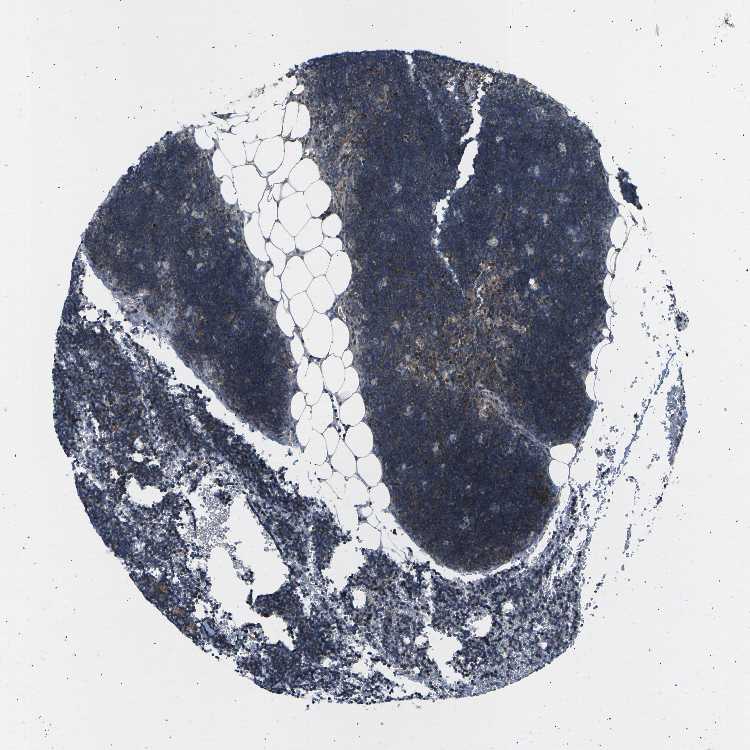

TISSUE PRIMARY DATA LYMPH NODE Show tissue menu

Lymph node

LYMPH NODE - Expression summary

Protein expression

Lymph nodei

On the top, protein expression in current human tissue, based on all annotated cell types, is reported with the units not detected (n), low (l), medium (m) and high (h). Underneath, protein expression in each annotated cell type are reported using the same units.

Protein expression data is based on knowledge-based annotation. For genes where more than one antibody has been used, a collective score is set.

Germinal center cells: High

Non-germinal center cells: Medium

LYMPH NODE - Antibody stainingi

Antibody staining in the annotated cell types in the current human tissue is reported as not detected, low, medium, or high, based on conventional immunohistochemistry profiling in selected tissues. This score is based on the combination of the staining intensity and fraction of stained cells.

Each image is clickable and will lead to virtual microscopy that enables deeper exploration of all samples and also displays staining intensity scores, fraction scores and subcellular localization as well as patient and tissue information for each sample.

Antibody HPA003221Antibody CAB003853Antibody CAB013520

Germinal center cells HighMediumLow

Non-germinal center cells MediumMediumHigh